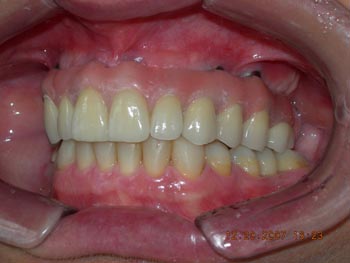

Diagnóstico preliminar das principais ocorrências: Prótese total na maxila em articulação com dentição natural inferior, apresentando acentuado trespasse horizontal (mordida profunda) e inclinações linguais generalizadas, com ausência do primeiro molar inferior esquerdo.

Vista lateral direita após correção ortodôntica e finalização da protocolo com dentes individuais em metalocerâmica

Vista frontal após correção ortodôntica e finalização da protocolo com dentes individuais em metalocerâmica

Vista lateral esquerda após correção ortodôntica e finalização da protocolo com dentes individuais em metalocerâmica